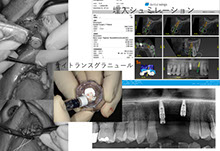

当院のインプラント治療はデジタルCTデータを基に専用ソフトにてインプラント手術をシミュレーションし、手術から最終補綴まで安心、安全そして長期安定性を目指し最新のプロトコルによるデジタルシステムで対応しています。また、骨の状態により骨増生、サイナスリフト、ソケットリフト、ボーンスプレッディング等、様々な対応をいたします。

様々なデジタル機器を導入し治療精度の向上に努めています